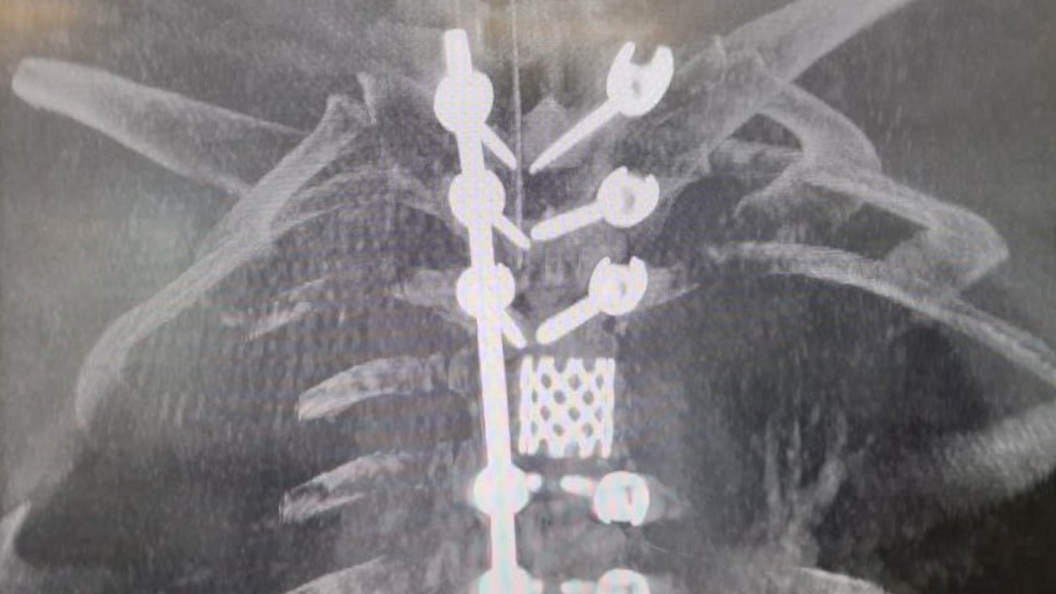

Клинические случаи: компрессионные переломы позвоночника